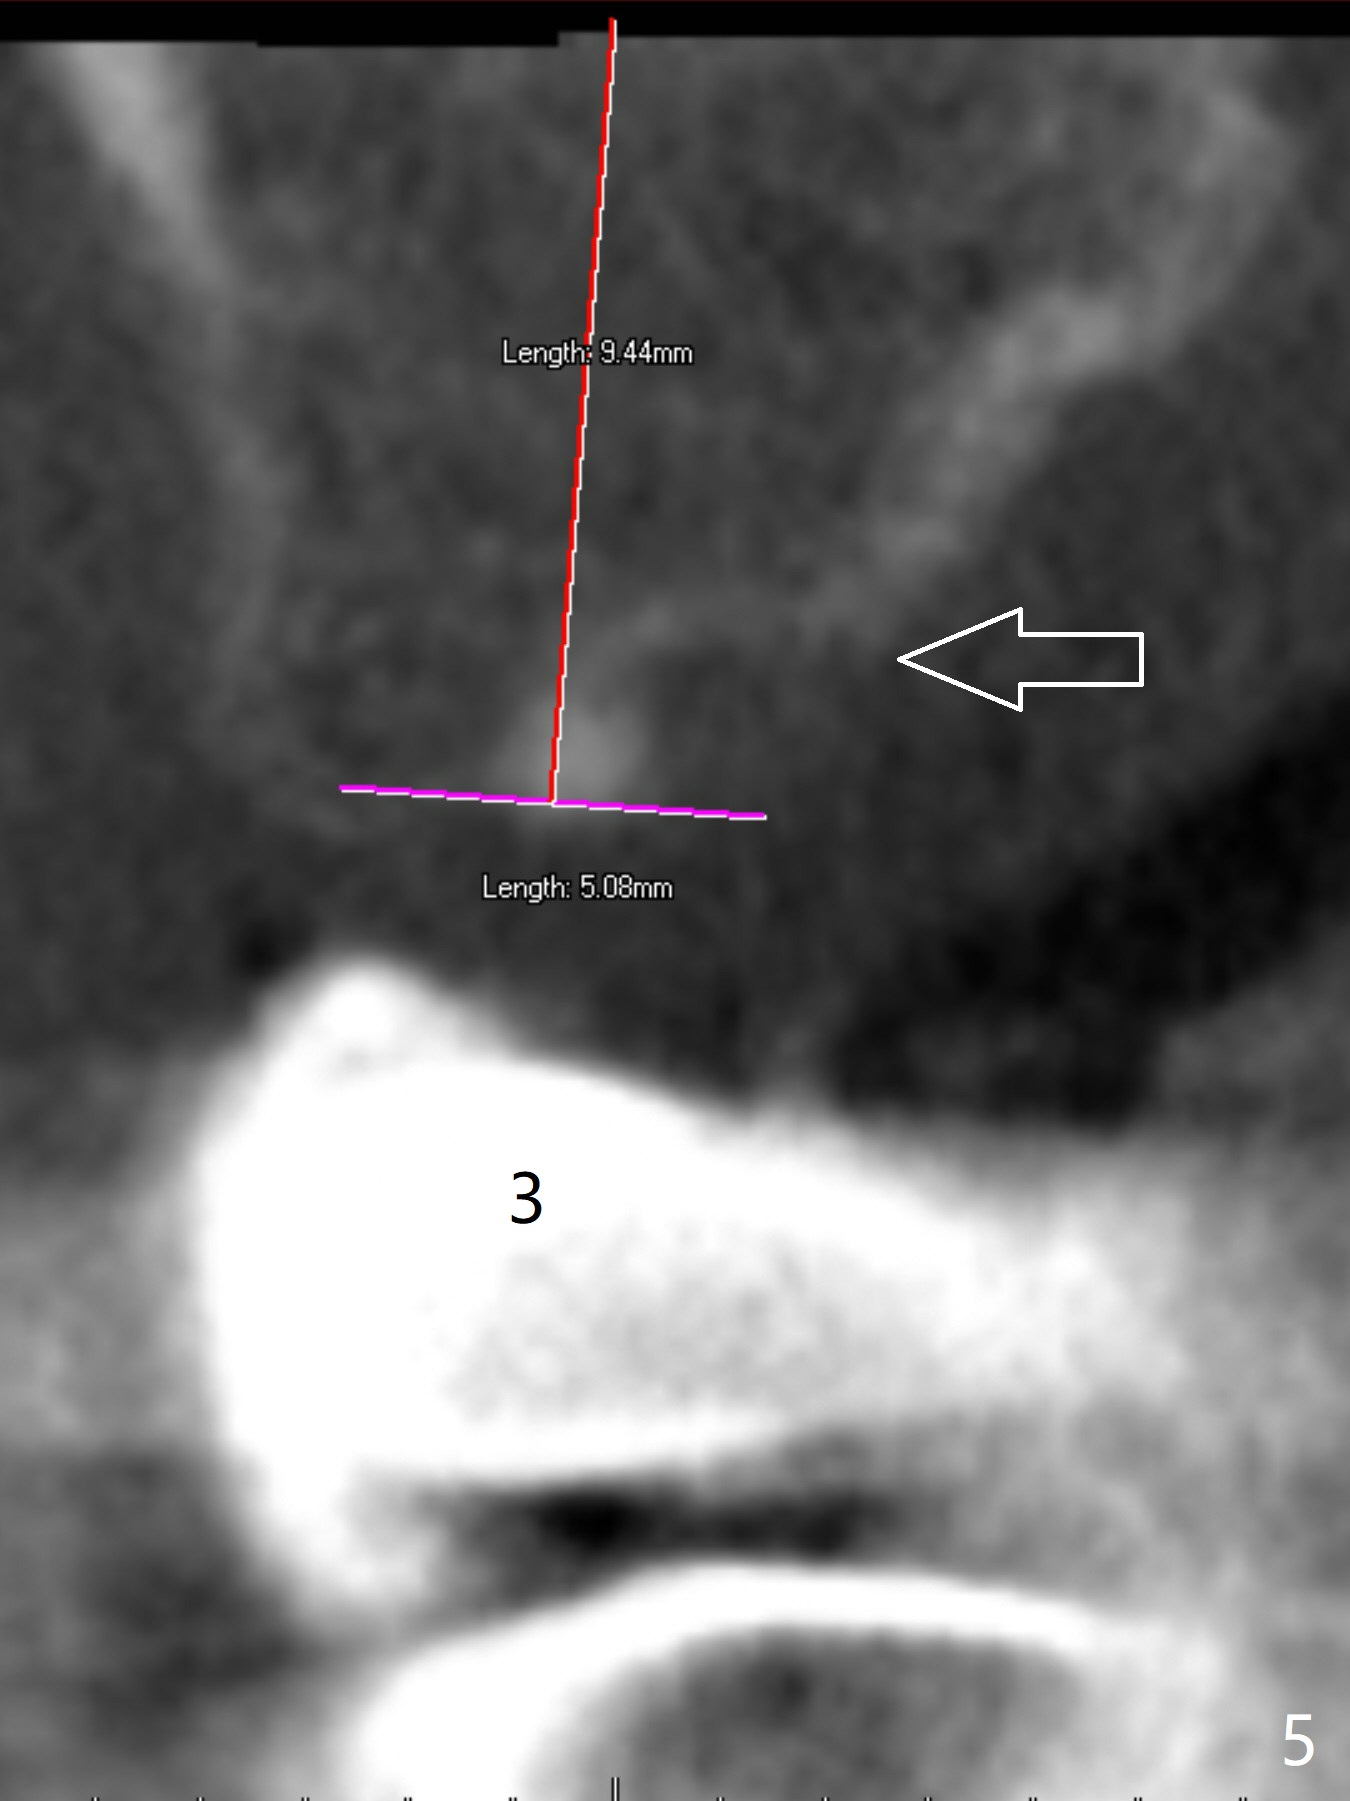

A 43-year-old woman has a failing upper right bridge (Fig.1: #2-5). While the abutment at #5 has apparently palatal open margin (Fig.2,3) and that at #4 has severe palatal bone loss (Fig.4 arrow), that at #2 has the poorest prognosis (Fig.6,7). Panoramic X-ray or PAs will be taken because of CBCT cone cut when the patient returns for #30 and 31 post-implant follow-up. Alginate impression will be taken for the upper right quadrant for provisional. The bridge will be sectioned between #3 and 5 (Fig.1 red lines) to determine salvageability of the abutments at # 4 and 5. If the latter are ok, the abutment at #2 will be extracted (expected to be loose) and implants will be placed at #2 and 3. If #4 is bad while #5 is ok, the former will be extracted and implants will be placed at #2 and 4 with a bridge. If #5 is bad while #4 is ok, implants will be placed at #2, 3 and 5.